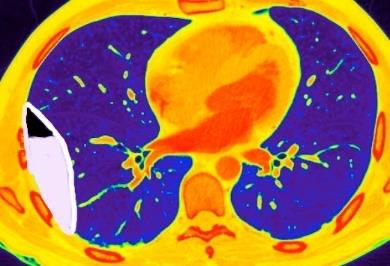

Pleura “parietal” radiológica (TC)

La pleura “normal” no se visualiza en los estudios de TC.

(En el esquema se corresponde con la línea azul entre el espacio extrapleural verde y el pulmón morado)

En estudios de TCAR puede verse la banda de grasa extrapleural adyacente a la pleura parietal